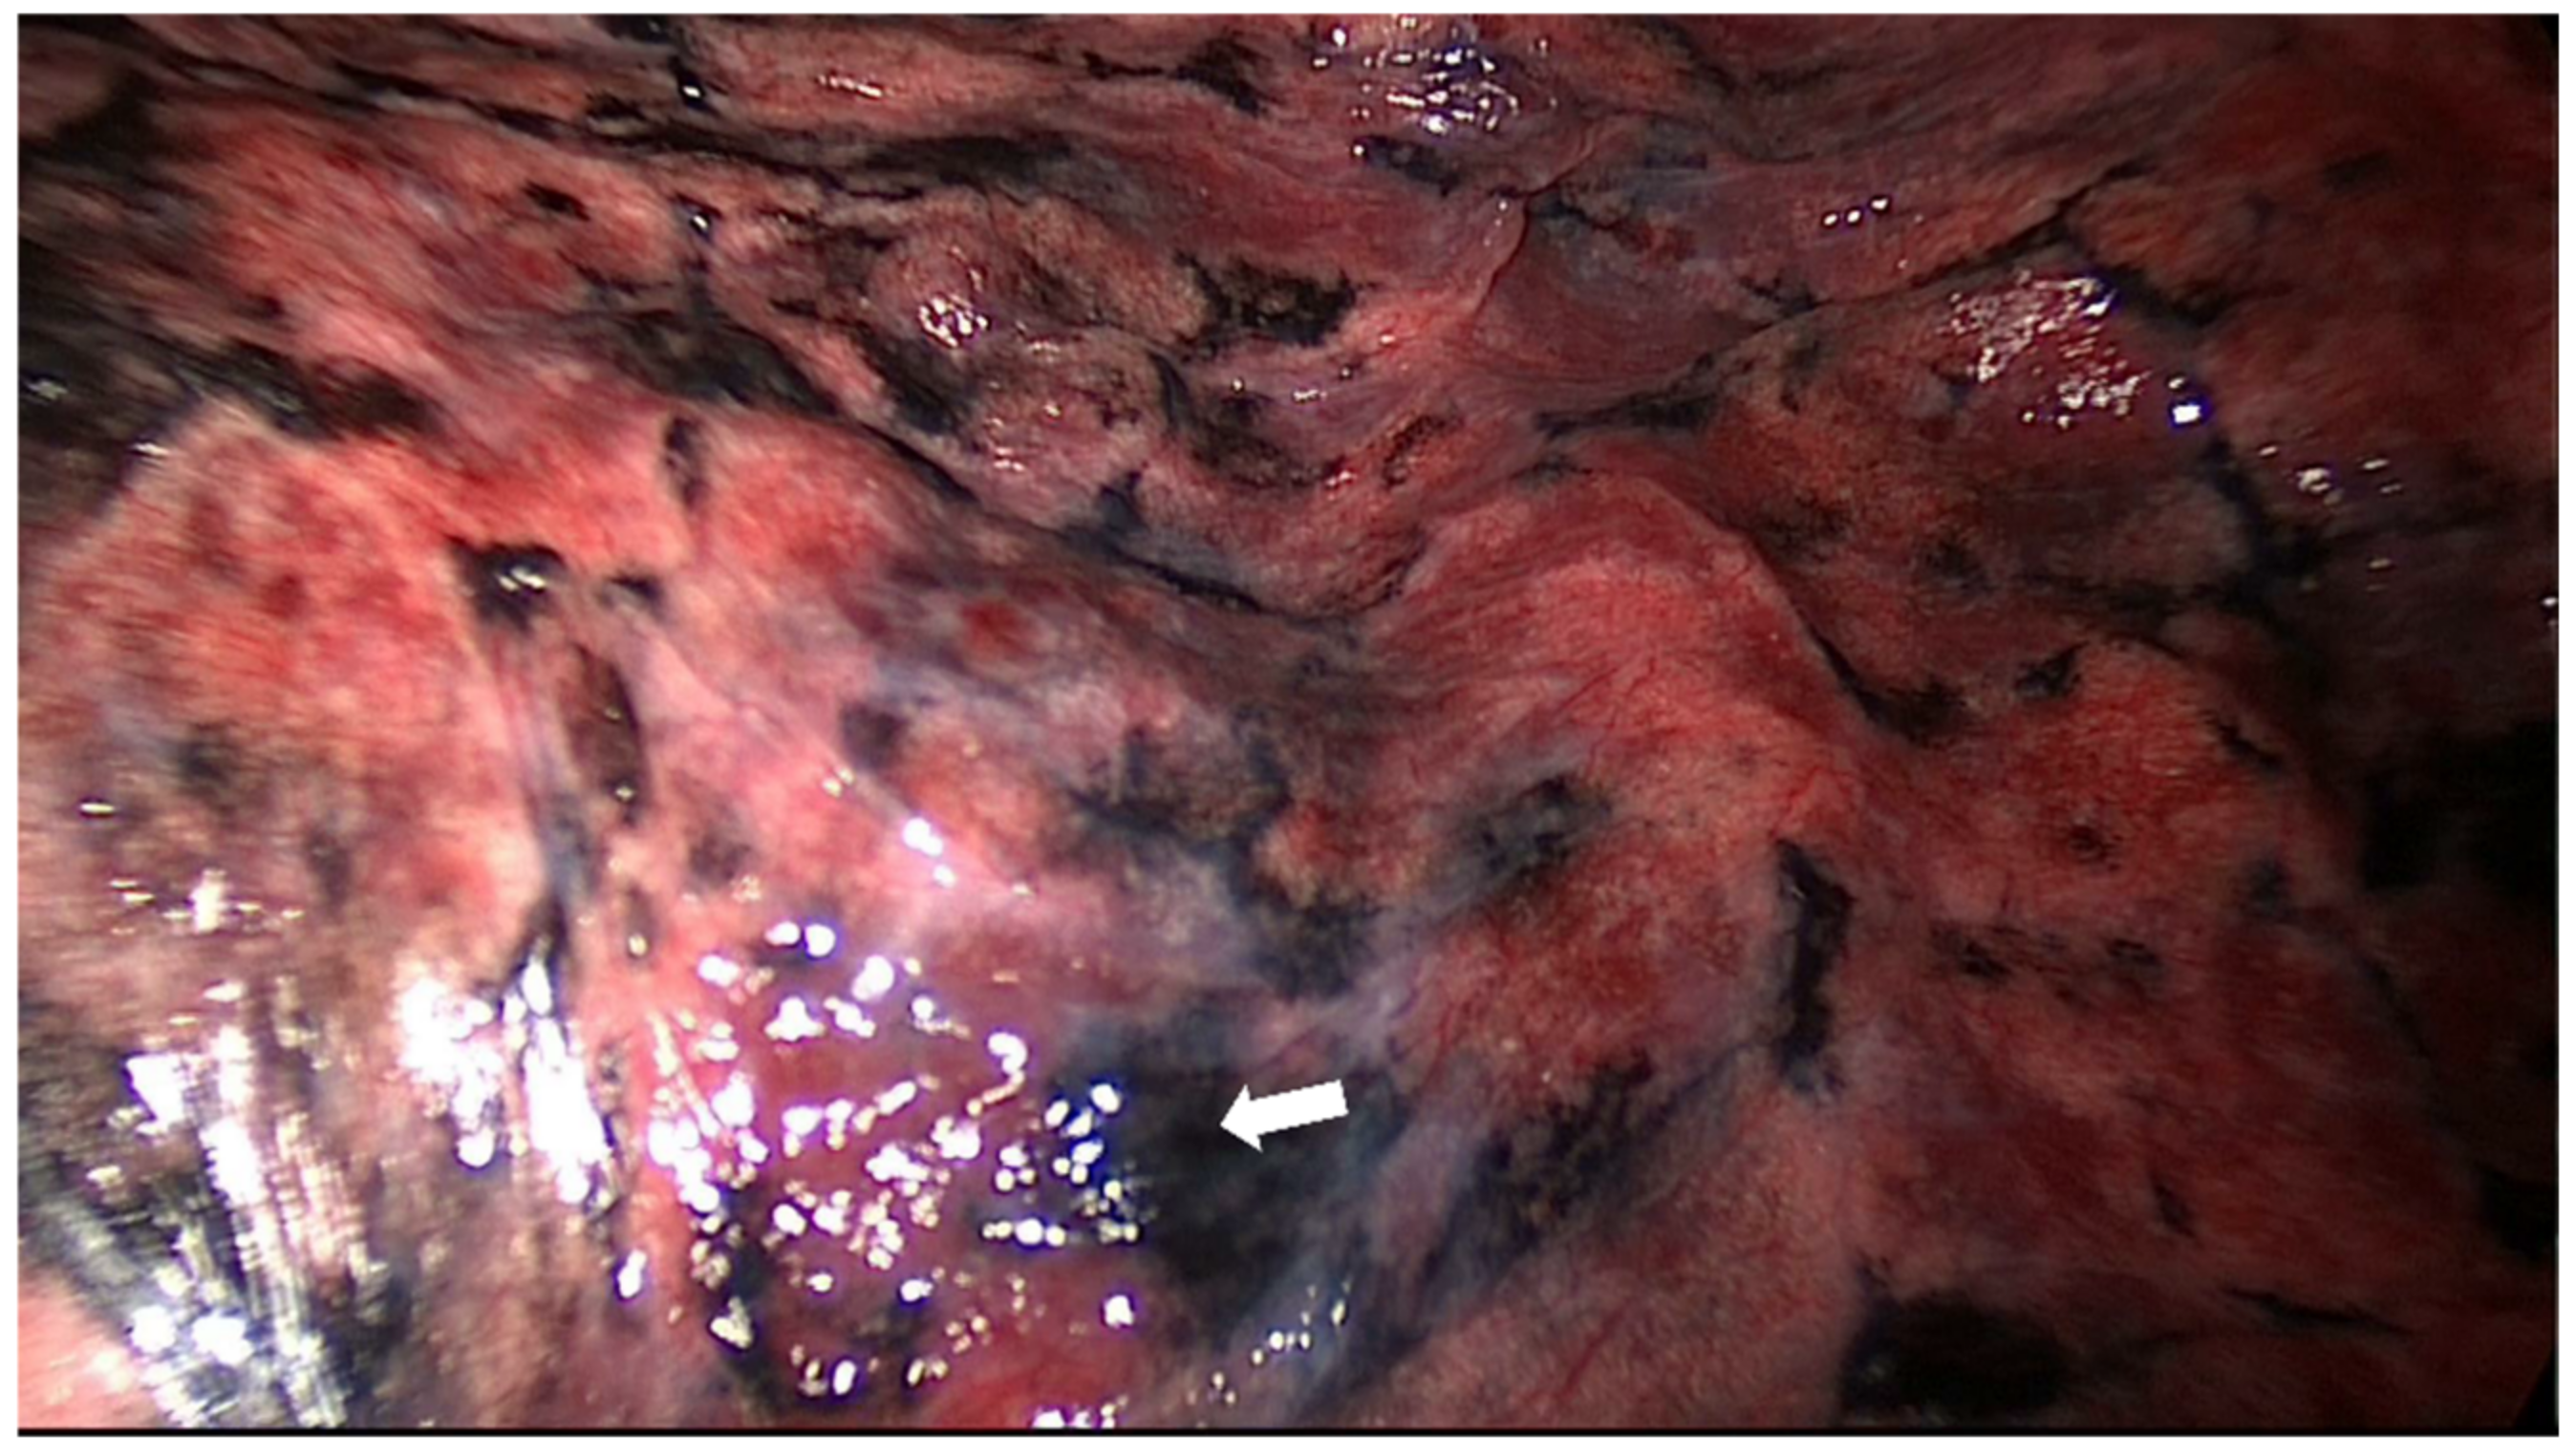

| Identification of the pleural tattoo, n (%) | 172 (98.3%) |